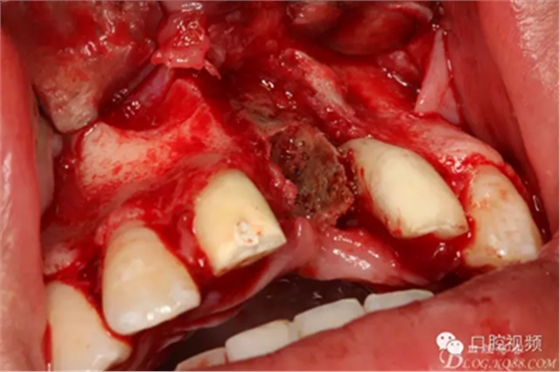

圖9.牙槽骨壞死達鼻底

圖10.摘除死骨、并刮除周圍炎性肉芽組織。